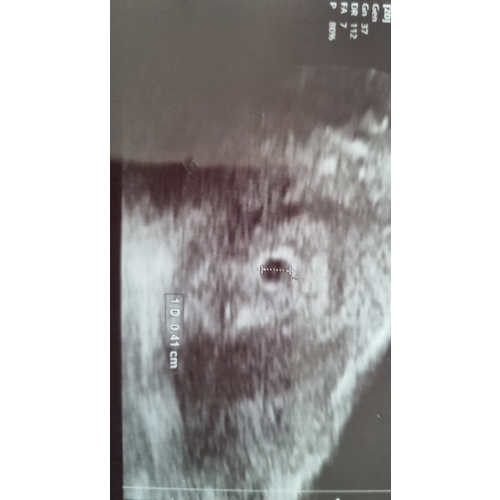

Op de echo kon je wel goed het vruchtzakje zien, maar was te klein voor 6 weken, hij was 11mm.

Ik ben terug gezet op 5+3. Verder konden ze nog niks vinden in de vruchtzak. Nu vrijdag moet ik weer heen en ben dan 6+2 en ik hoop echt dat we dan wat gaan zien. 🍀

Ik heb het ook lege vruchtzak

Alleen ben wat verder 6,3 toen!